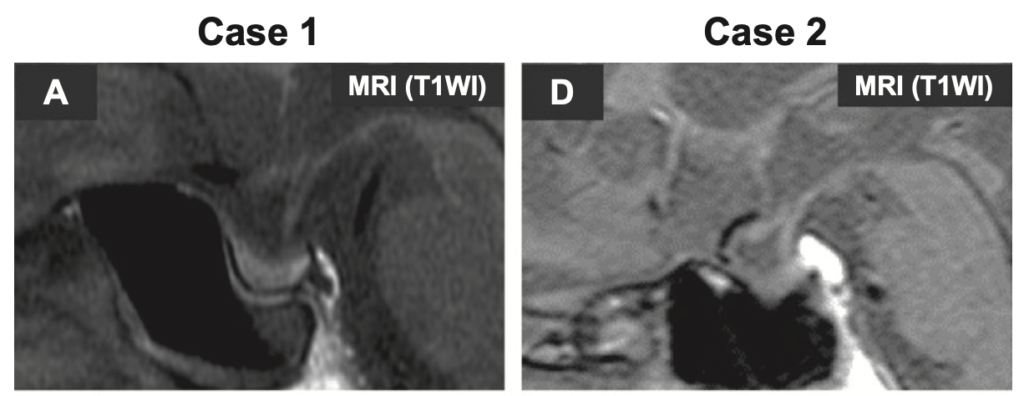

下垂体MRIでは前葉が軽度萎縮もしくは正常。

下垂体MRIでは明らかな異常が認められないため、原因不明の中枢性甲状腺機能低下症と診断されることが多い。しかし、造影MRIを行うと一部の患者では不均一な増強を伴うわずかに萎縮した下垂体前葉が認められる。